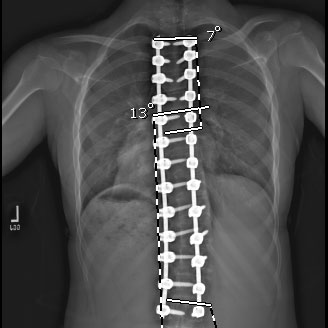

The goals of scoliosis surgery, performed by Dr. Geck in Austin Texas, are to obtain curve correction and to prevent curve progression, thus improving the patient's future potential for pain and deformity.Thoracoscopic SurgeryVideo assisted thoracoscopic surgery uses techniques for minimal invasion of the chest wall or thoracic cavity.